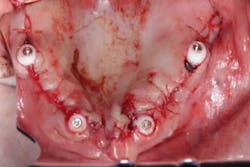

Surgery commenced. Implants on the lower arch were placed first (figures 7 and 8) and then we switched to the maxillary. The teeth were removed (figures 9 and 10) and the ridge was evened out (figures 11-13). The implants were aligned with the denture (figure 14) and then placed accordingly (figures 15-17). Healing caps were put on, and we were ready to start the restorative phase (figures 18-19).

The maxillary arch was indexed first as there was support from the palate to reference position (anterior/posterior) (figure 20). Then the lower was put into position to gain proper vertical dimension and occlusion. It, too, was then indexed; both upper and lower were given to the lab technician to start the conversion process. Next, impression copings were placed (one arch at a time) and secured with paperclips; a full-arch PVS impression was taken and likewise sent to the lab (figures 21-23). Finally, after the conversion process was completed, the bridges were secured in place on the multiunit abutments, torqued to 15nCm, and covered. Bite was adjusted and follow-up care was arranged (figures 24-26).